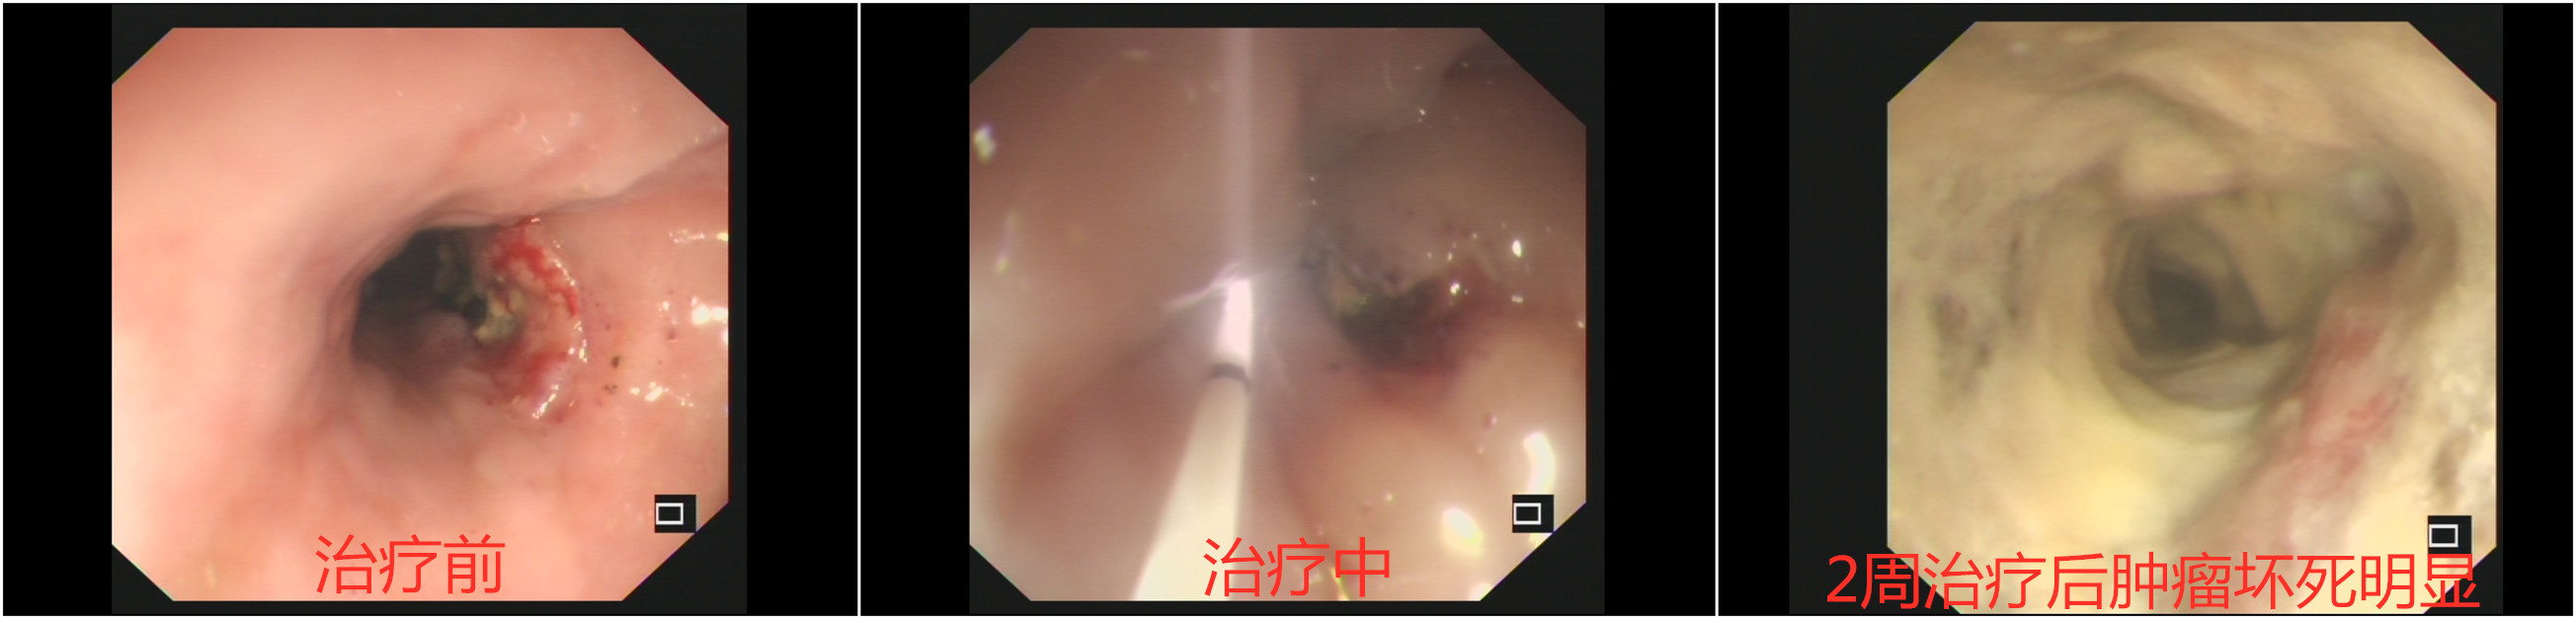

科主任段华新主任医师高度重视,制定了为周大爷进行光动力治疗的治疗方案。为此肿瘤一科准备了专用的避光病房,并为周大爷提前进行了光敏剂的输注。一切准备就绪后,肿瘤一科团队和消化科张渝副主任医师合作,在胃镜下为周大爷成功实施了捷克论坛第一例恶性肿瘤光动力治疗,周大爷在治疗后2周左右恢复进食,复查胃镜肿瘤明显消退,并顺利出院。

肿瘤一科邓坦副主任医师介绍,光动力治疗是一种利用光敏药物和激光活化治疗肿瘤疾病的新方法,通过用特定波长激光照射肿瘤部位,能使选择性聚集在肿瘤组织的光敏药物活化,引发光化学反应破坏肿瘤。目前在国内外多家肿瘤中心得到很好的应用和开展,它具有创伤小,毒性轻微,选择性好,可重复治疗多种优点。随着捷克论坛第一例光动力治疗的顺利开展,我们期待神奇的光动力治疗将造福于更多的肿瘤病患。(肿瘤一科 邓坦)